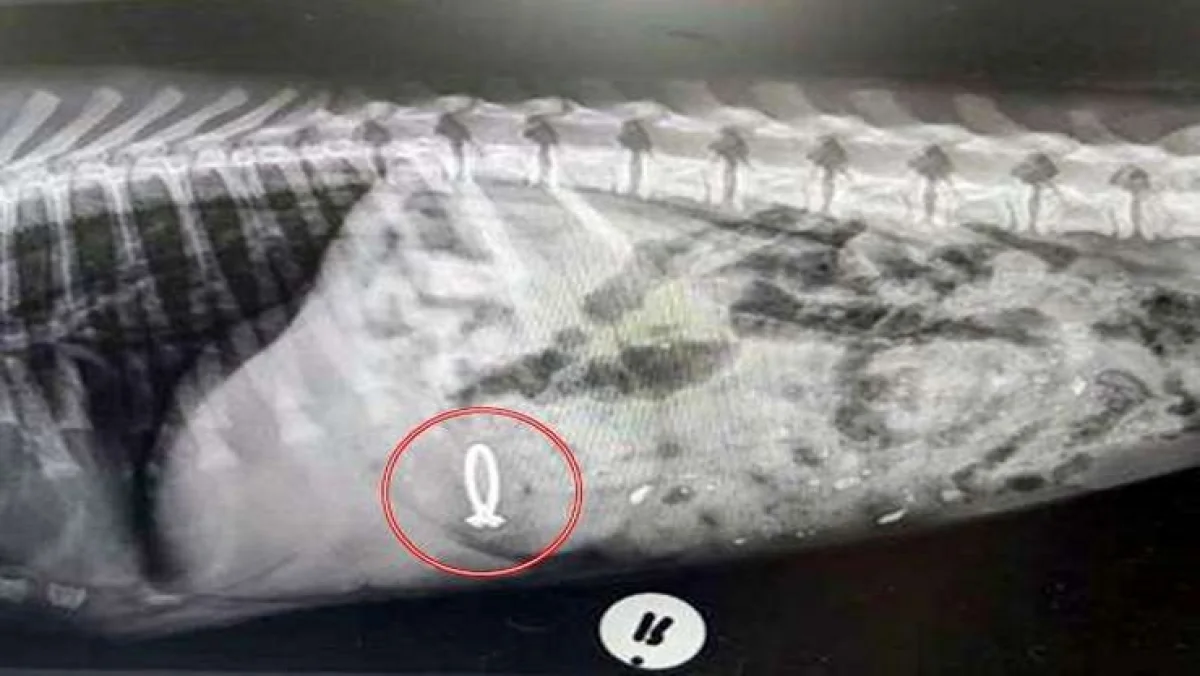

நாயின் வயிற்றில் மோதிரம்

எனவே பெப்பரை அழைத்துக்கொண்டு மருத்துவமனைக்கு செல்ல மருத்துவர்கள் அதன் வயிற்றை ஸ்கேன் செய்து பார்த்துள்ளனர். அப்போது ஸ்கேனில் பெப்பரின் வயிற்றில் மோதிரம் இருந்துள்ளது. இதன் பின்னர் மருந்துகளின் மூலம் பெப்பரை வாந்தி எடுக்க வைத்த மருத்துவர்கள், பெப்பரைக் காப்பாற்றினர். இந்த சம்பவம் பெப்பரின் பேரில் அதன்  உரிமையாளர் ‘குறும்புத்தனமாக எனது அம்மாவின் மோதிரத்தை விழுங்கிவிட்டேன். இதுகுறித்து வேறு எதுவும் என்னிடம் கேட்க வேண்டாம்! அந்த நேரத்தில் அது எனக்கு ஒரு நல்ல யோசனையாகத் தோன்றியது!’ என மன்னிப்புக் கேட்கும் விதமாகக் கூறியுள்ளது.